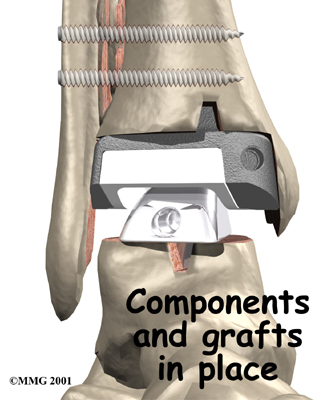

Because no one wants to lose the ability to move the ankle, much research has been done trying to perfect an

Because no one wants to lose the ability to move the ankle, much research has been done trying to perfect an